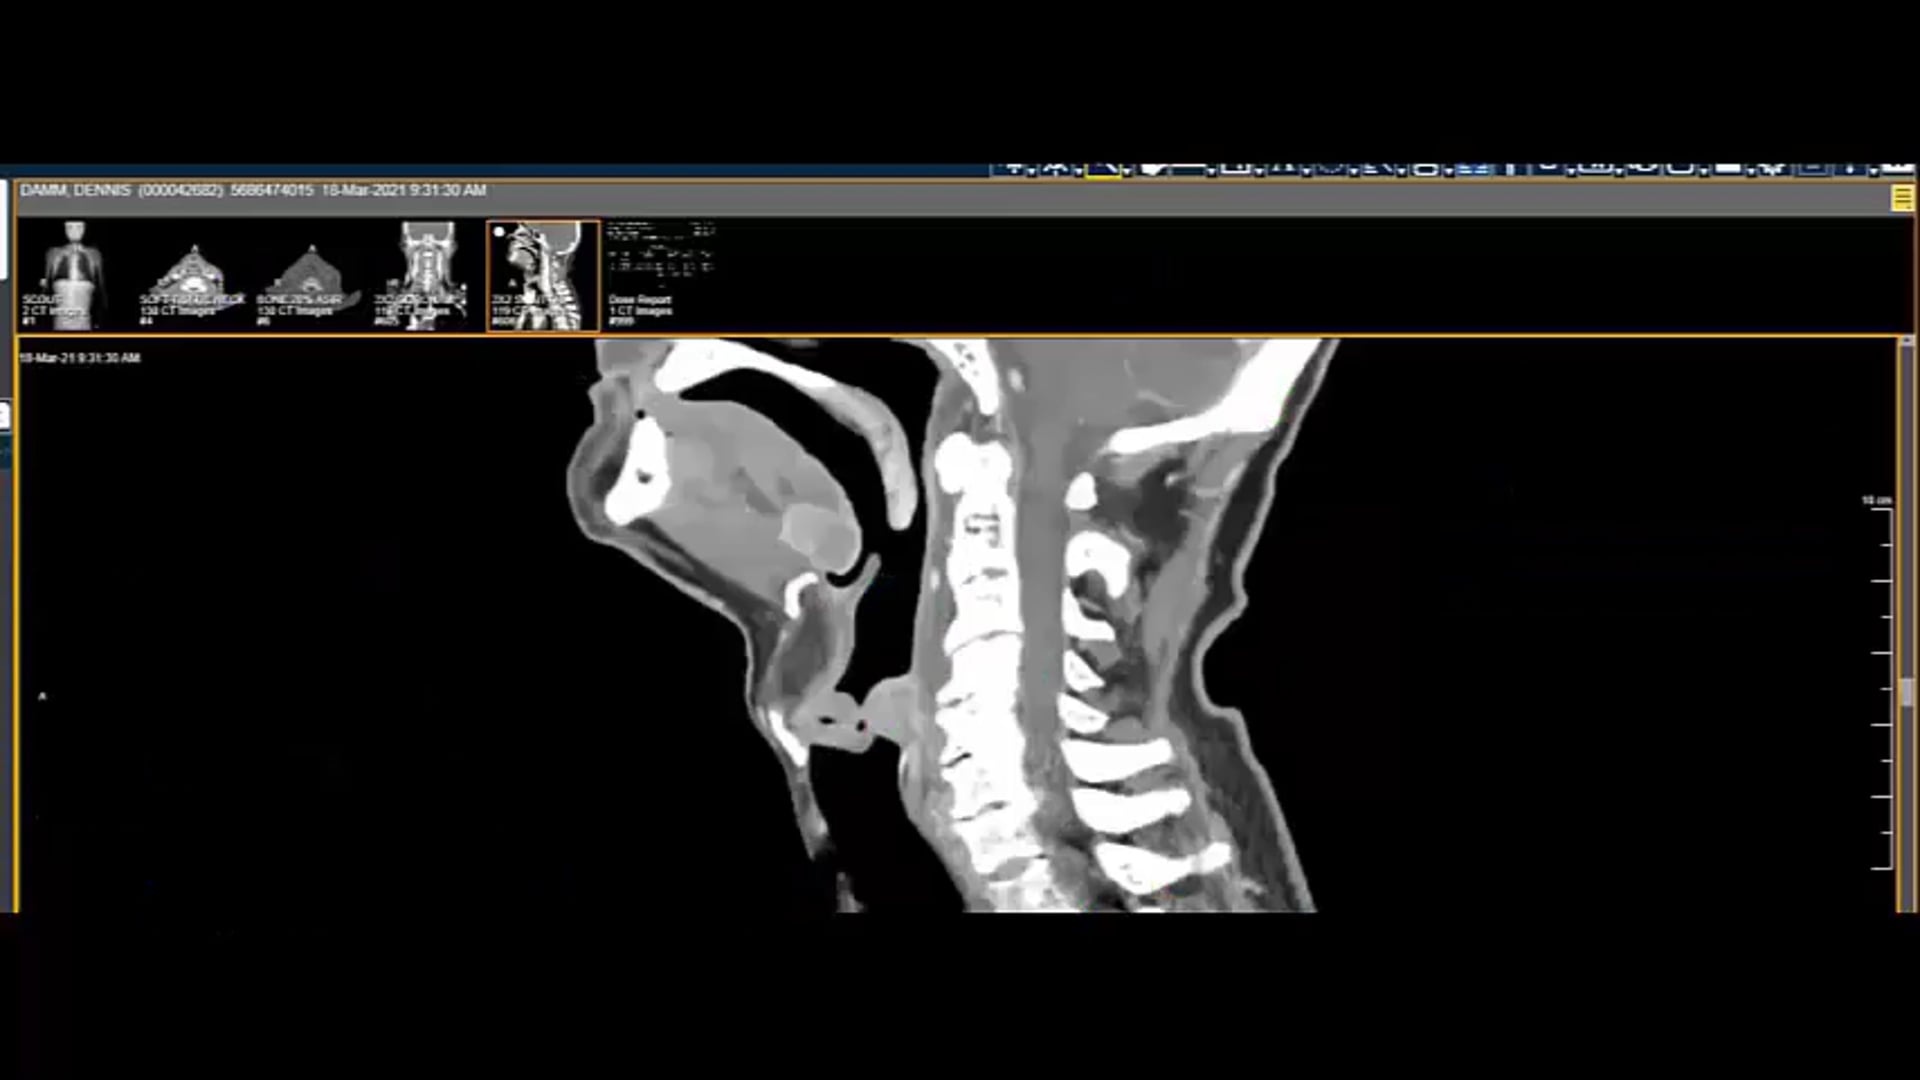

03/09/21- Dr. Kenneth Hu - Radiation Oncology - Head and Neck US

tongue-based cancer, dosimetry plan, treatment plan and contouring, contra-lateral node treatment, nasal pharynx treatment, bone invasive mass,